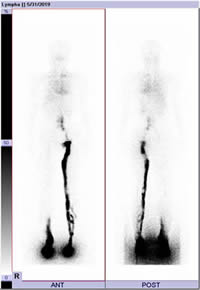

リンパシンチグラフィー(毎週水曜日・隔週金曜日)

アイソトープによる管造影(リンパシンチグラフィー)ではリンパ流をダイナミックに捉えることが可能であり、病期診断や手術適応の有無・治療効果の判断に有用な検査です。完全予約制のため希望される方は、まずは形成外科外来を受診してください(月・水)。

図:リンパシンチグラフィー 右下肢続発性リンパ浮腫

右下腿リンパ液の皮下への漏出を認める